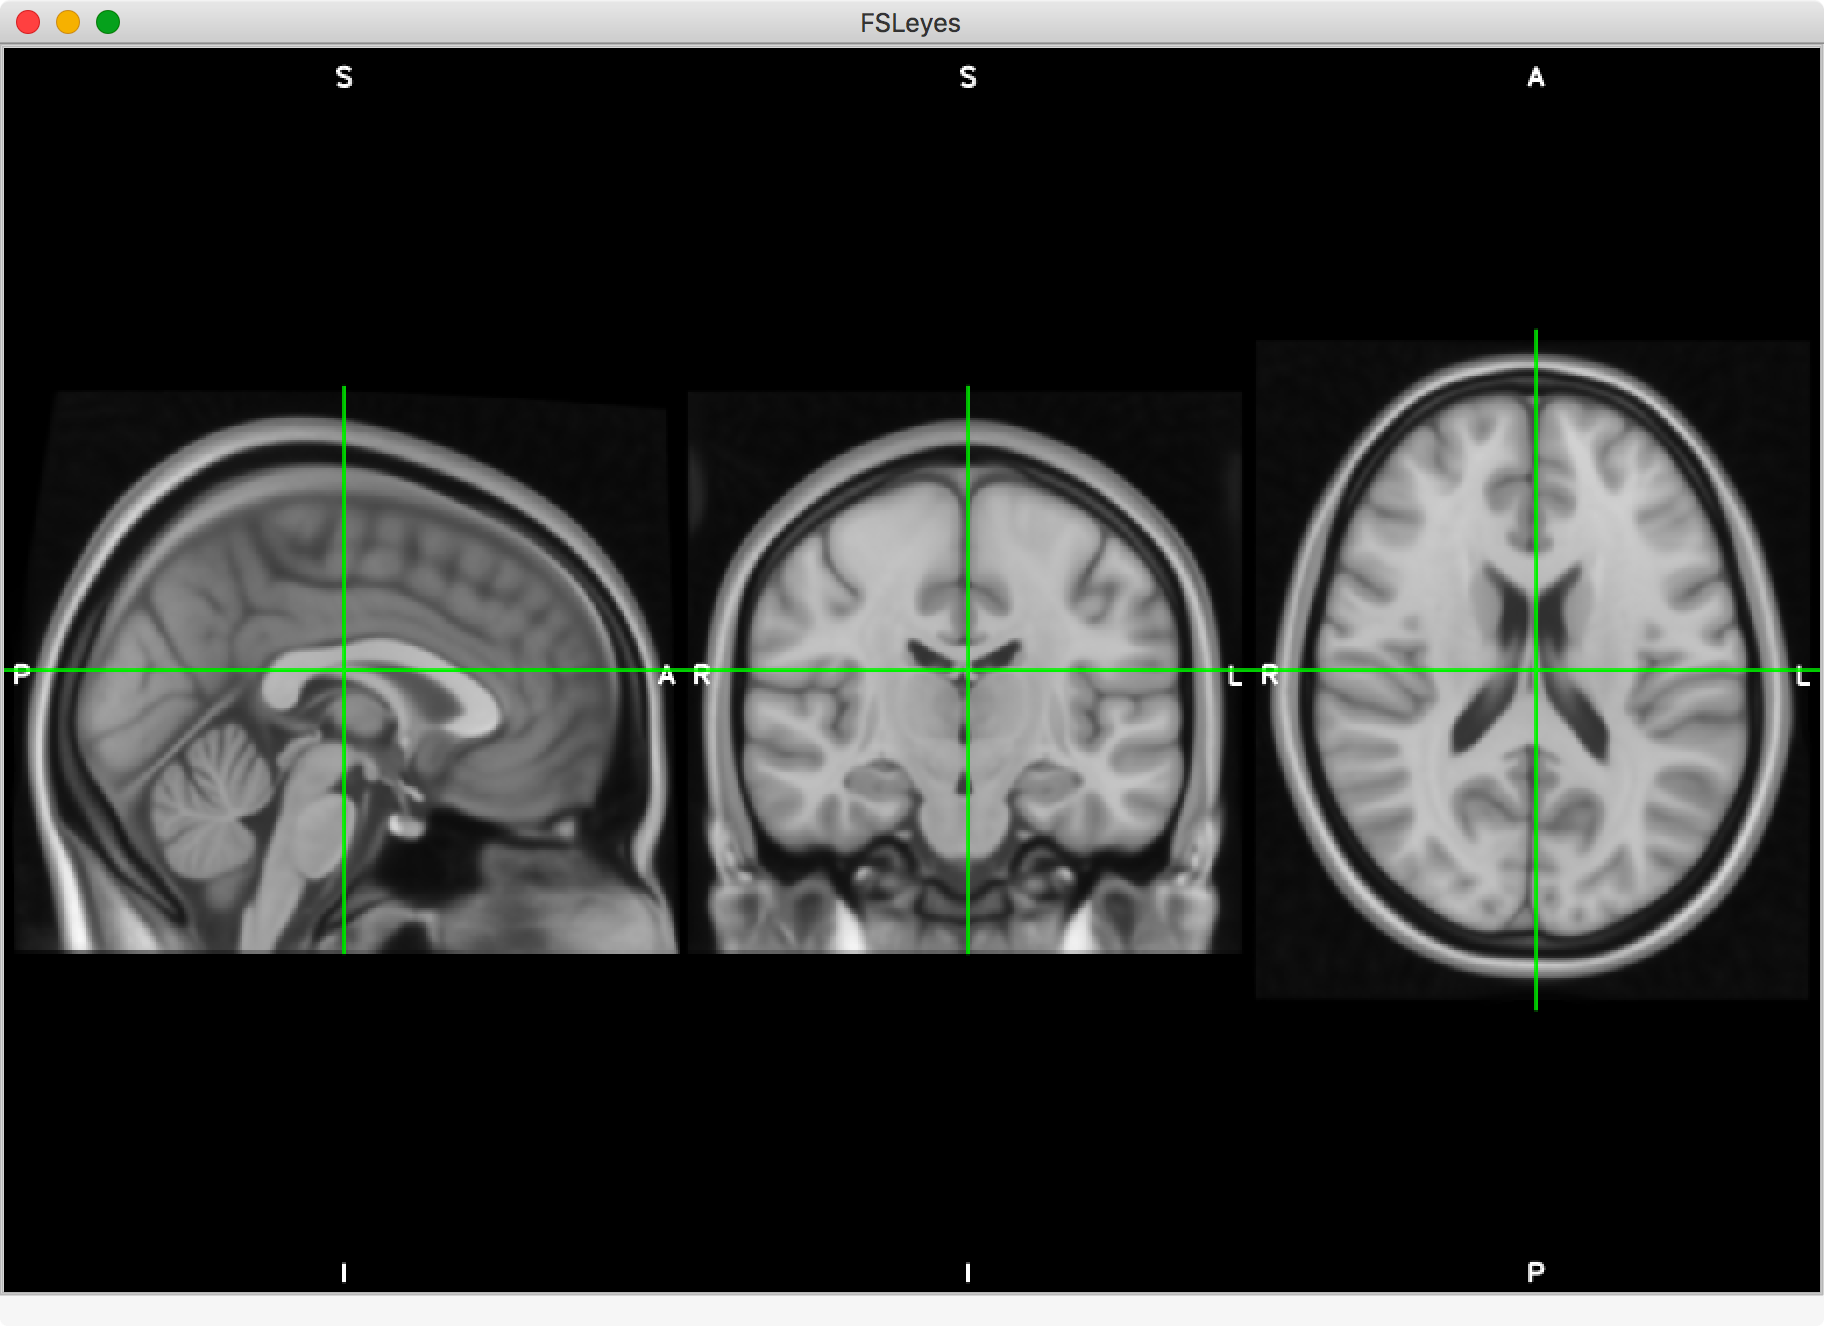

This is the default FSLeyes layout, inspired by FSLView, and useful for general image viewing and editing.